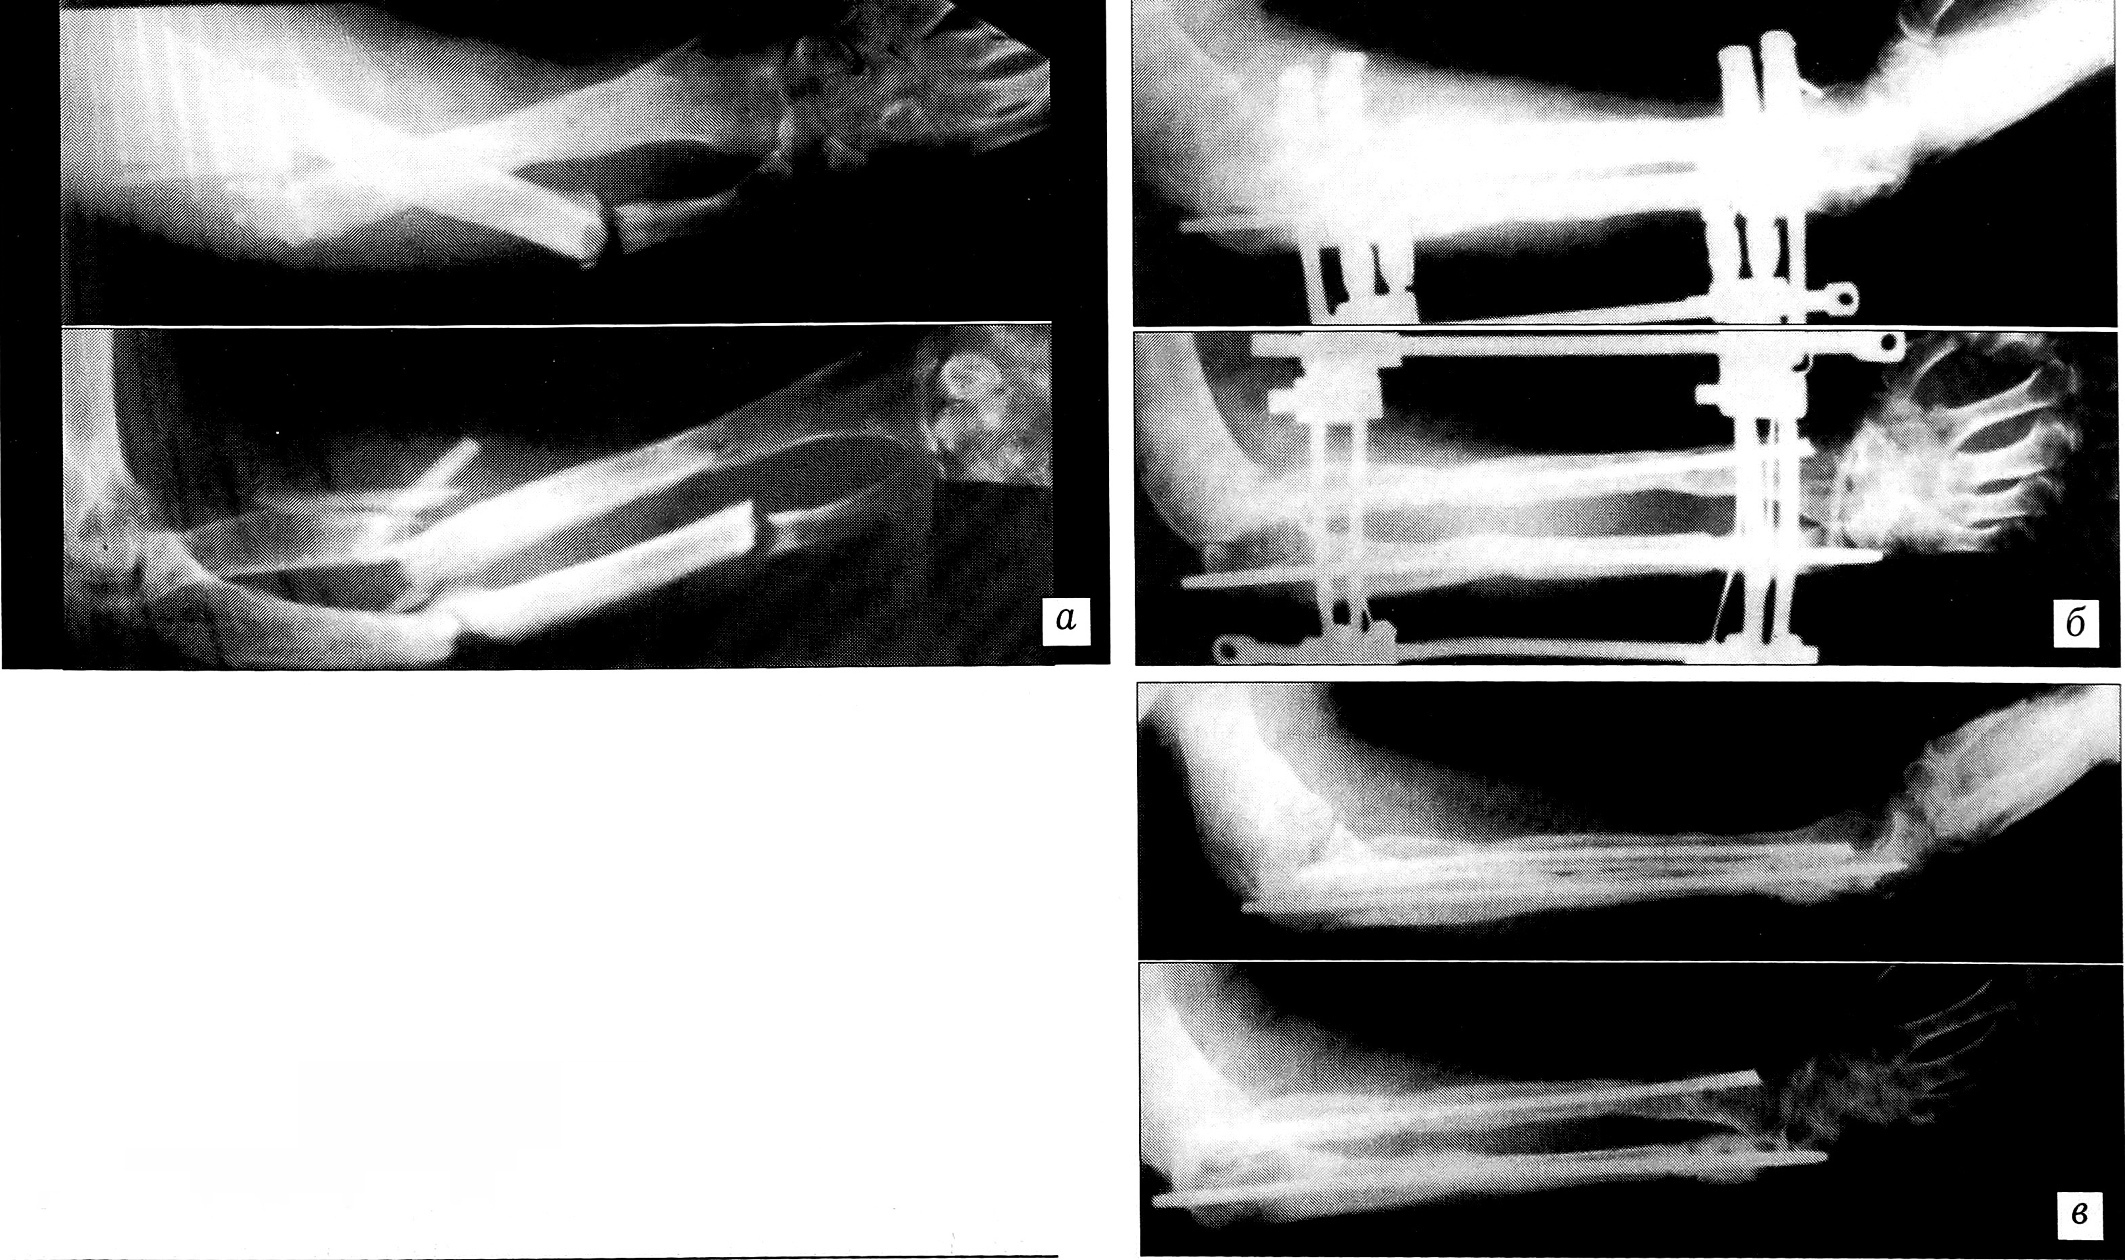

Пример 7. Больной П ., 29 лет, поступил в ЦИТО по поводу застарелых двойных переломов лучевой и локтевой костей (рис. 7, а). По месту жительства пациенту через 2 нед после травмы был произведен интрамедуллярный остеосинтез обеих костей предплечья штифтами Богданова — переломы не срослись. Наложен облегченный аппарат чрескостной фиксации, состоящий из четырех спиц и скоб (рис. 7, б). Через 3 мес клинически и рентгенологически констатирована консолидация обоих переломов (рис. 7, в).

Рис. 7. Пример 7.Рентгенограммы больного П.a — двойные переломы лучевой и локтевой костей;б — несросшиеся переломы обеих костей после интрамедуллярного остеосинтеза. Наложен аппарат чрескостной фиксации;в — через 3 мес: переломы срослись, аппарат снят.